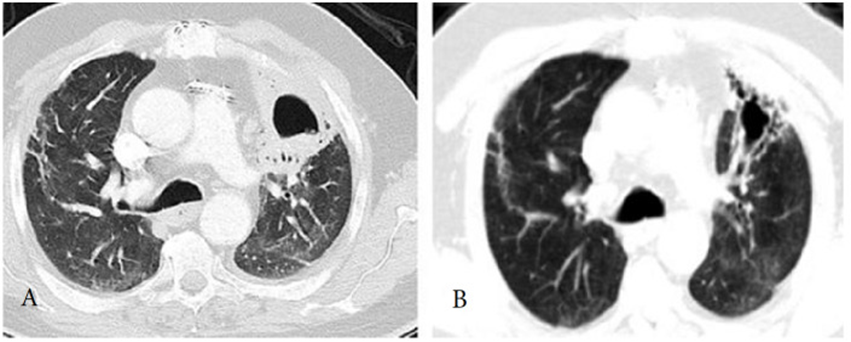

A: CT ngực của bệnh nhân cho thấy có một tổn thương hang ở thùy trên bên trái vào tuần 12 sau nhiễm COVID. B: CT cho thấy thoái triển tổn thương sau 6 tuần điều trị kháng sinh. (From archives of Aydın Yılmaz)